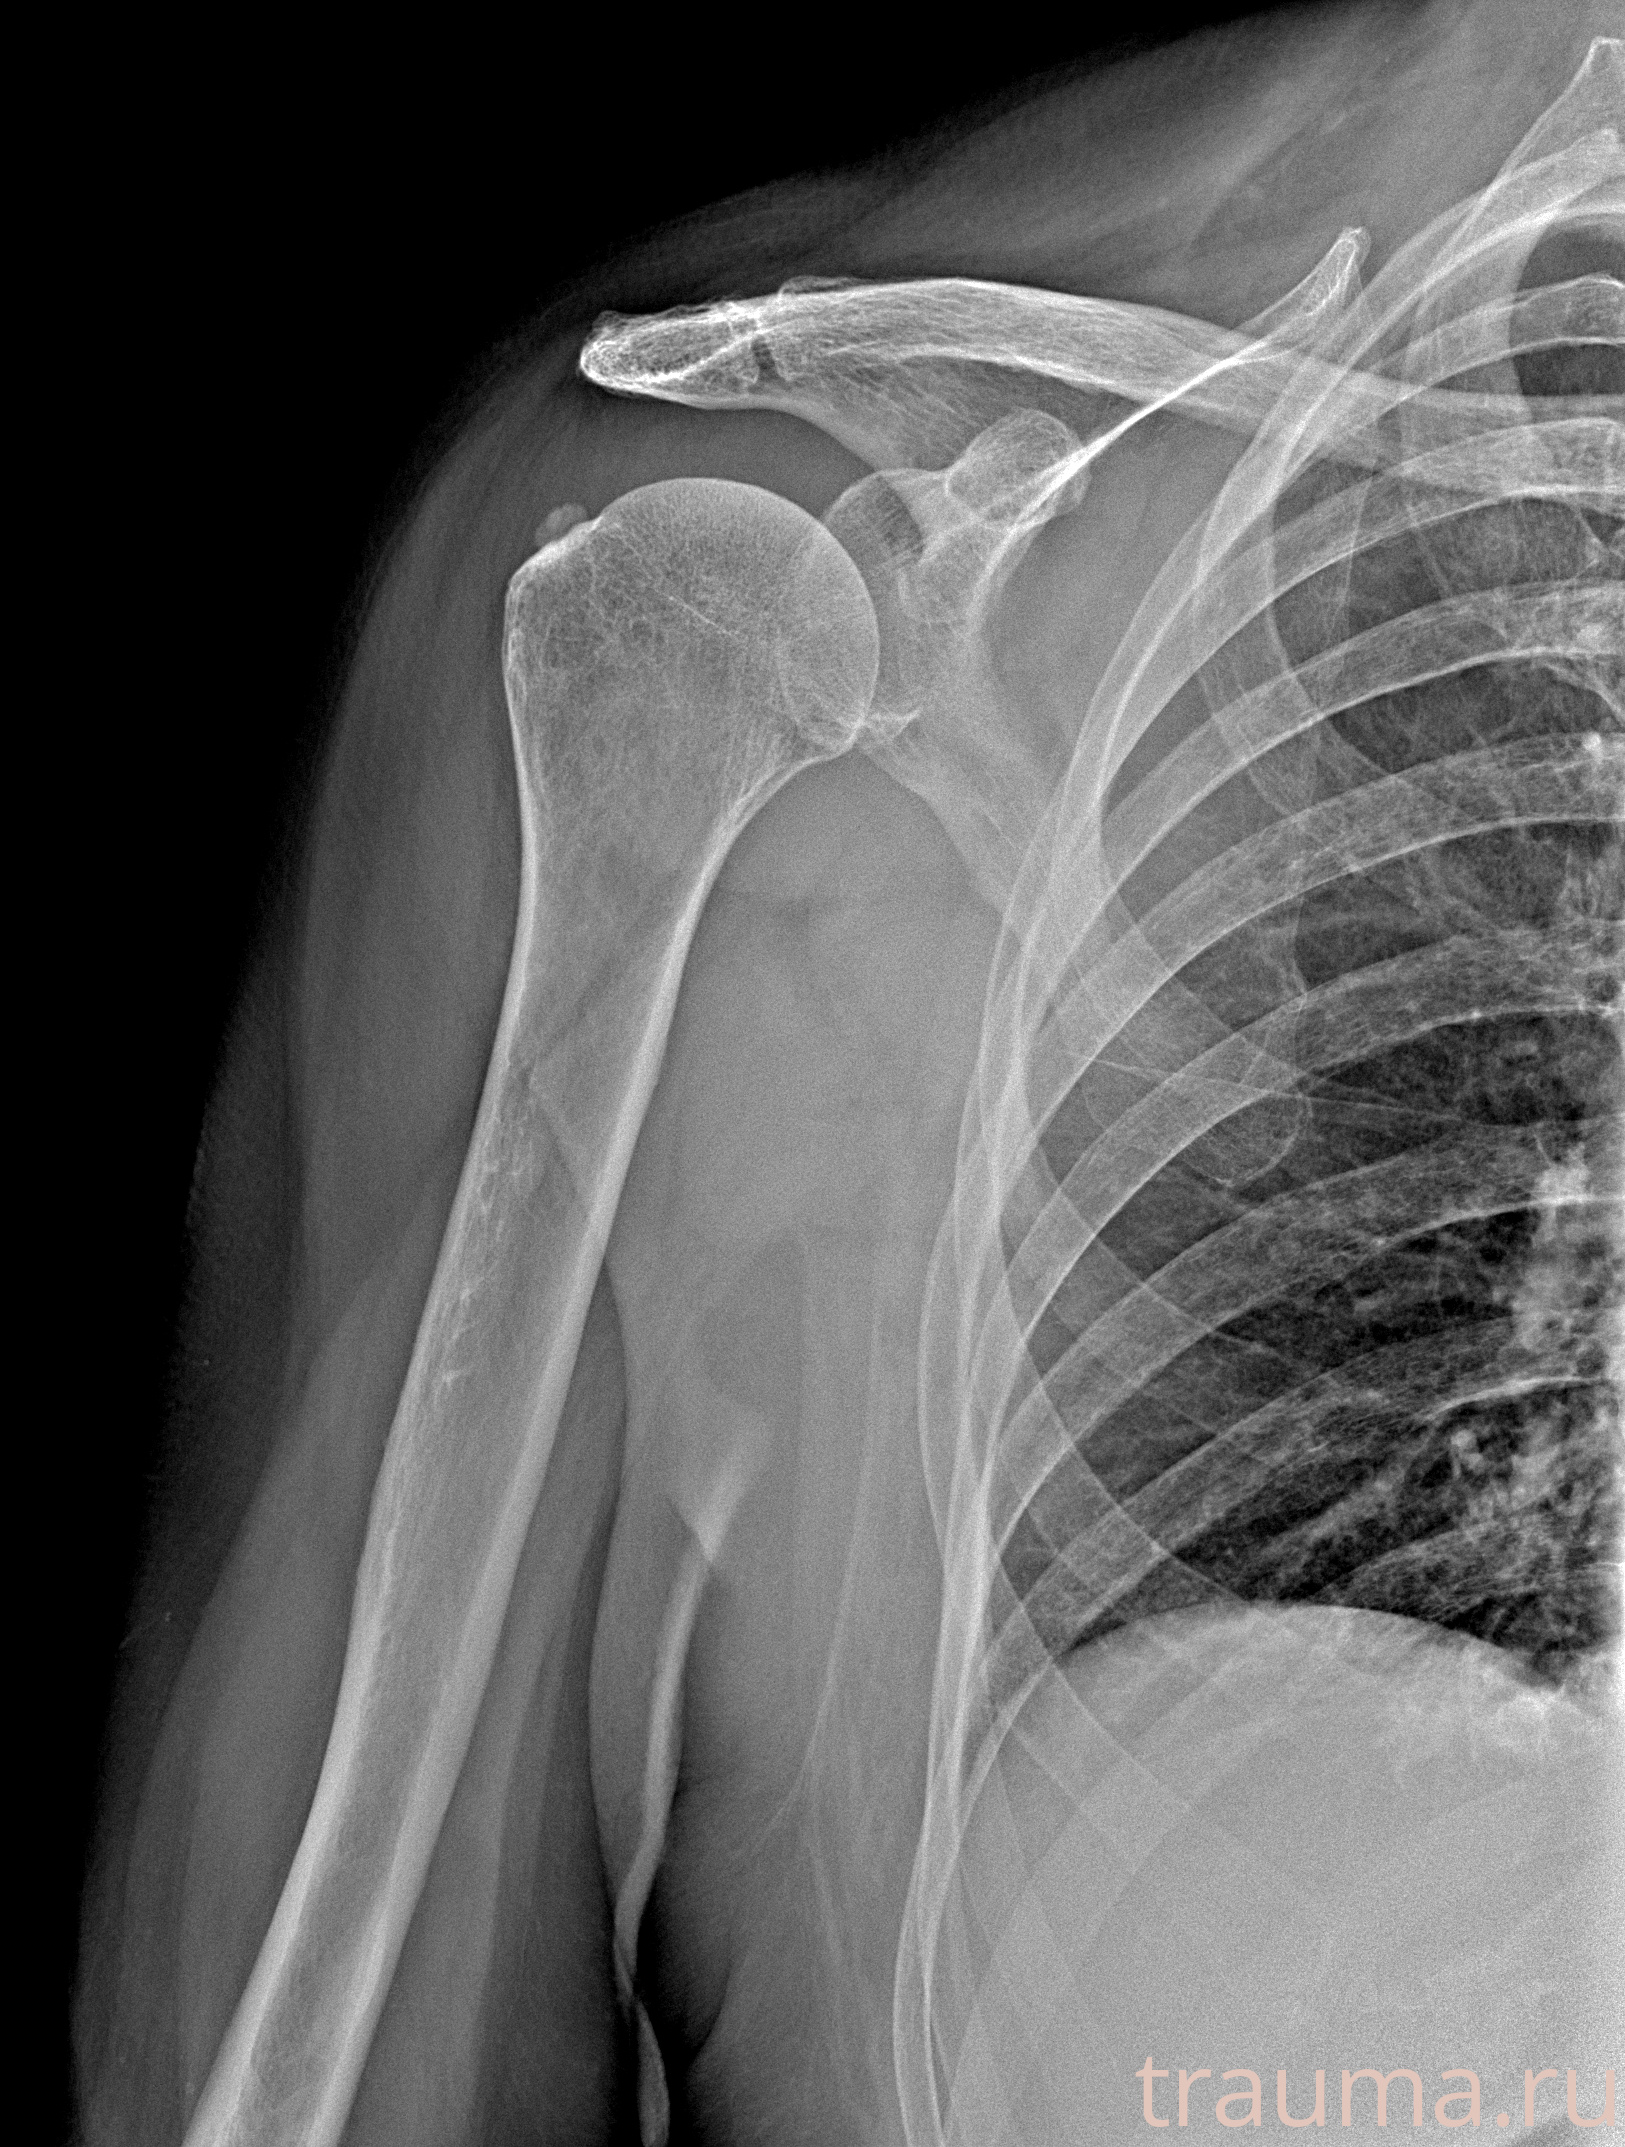

Рентген на дому: по вашему адресу приезжает врач-рентгенолог, травматолог-ортопед с мобильным рентгеновским аппаратом, проводит диагностику травмы или заболевания, делает необходимые рентгенограммы, дает рекомендации по дальнейшему лечению. Получить качественные снимки в домашних условиях возможно благодаря уникальной методике, разработанной МосРентген Центром для института  Склифосовского

при переломе шейки бедра и пневмонии от компании МосРентген Центр - партнера Института имени Склифосовского